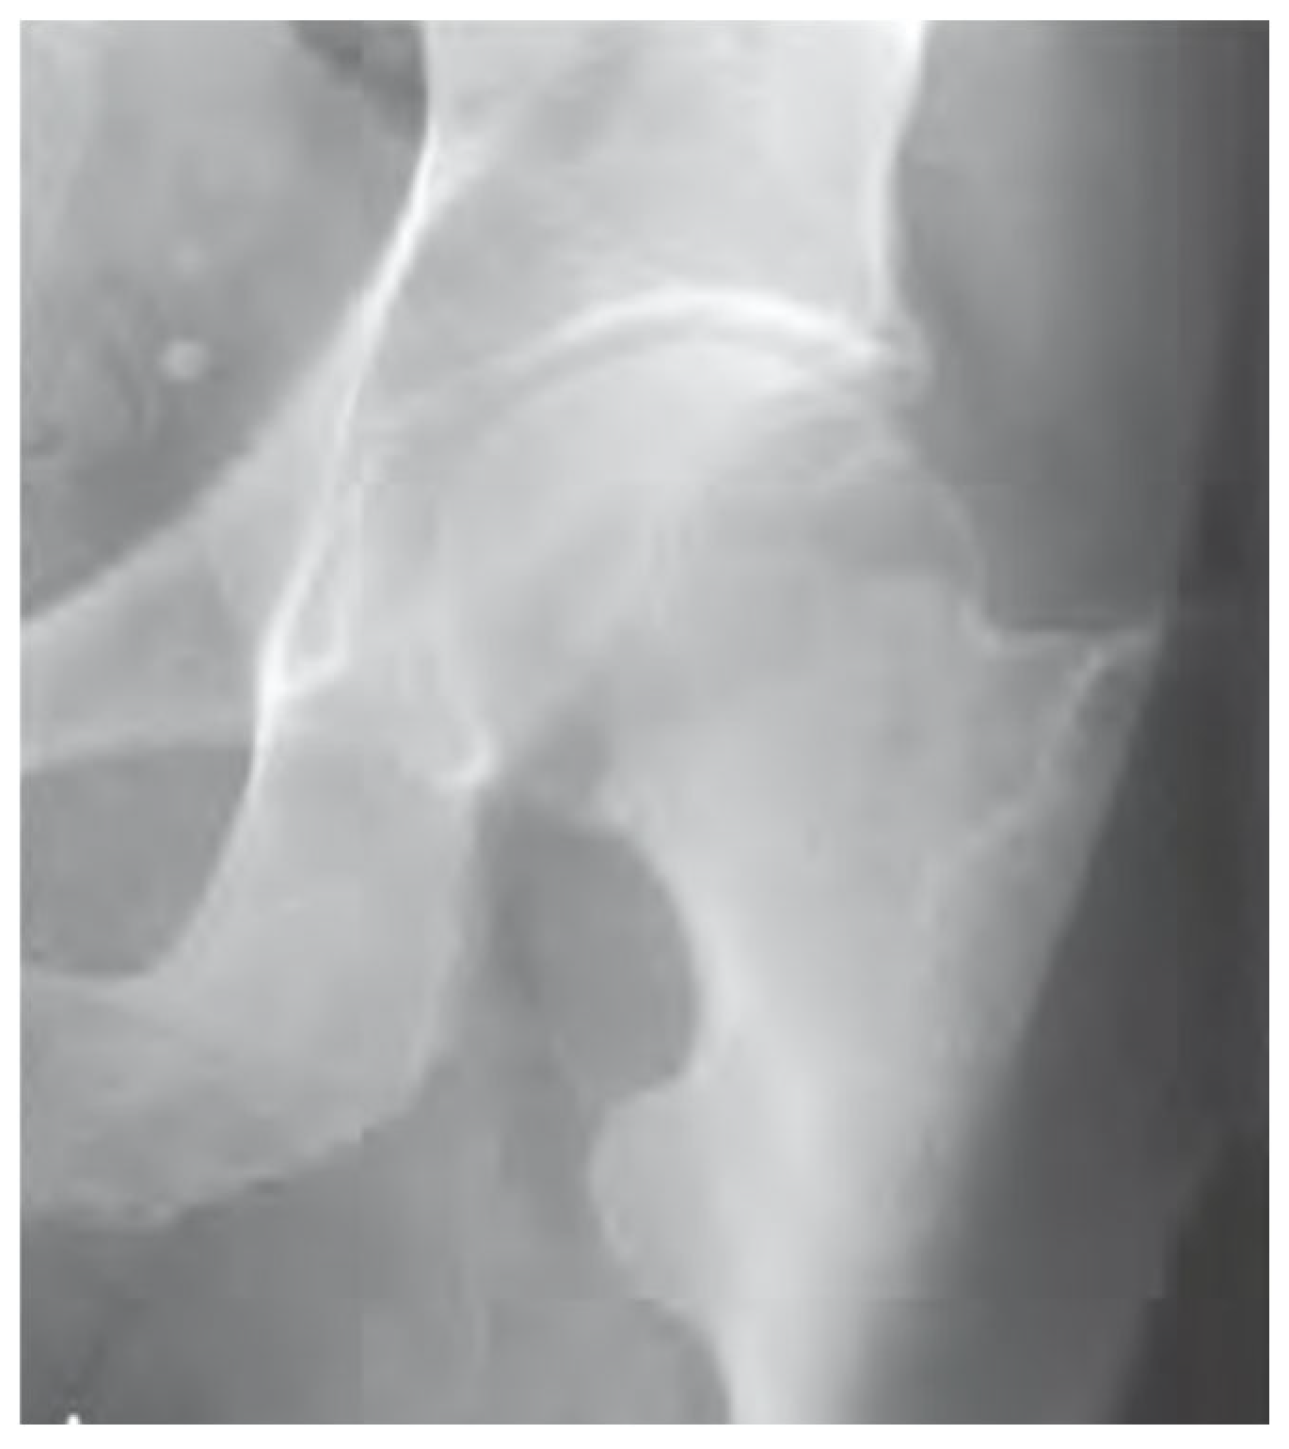

- Type 2: complete undisplaced (Figure 1)